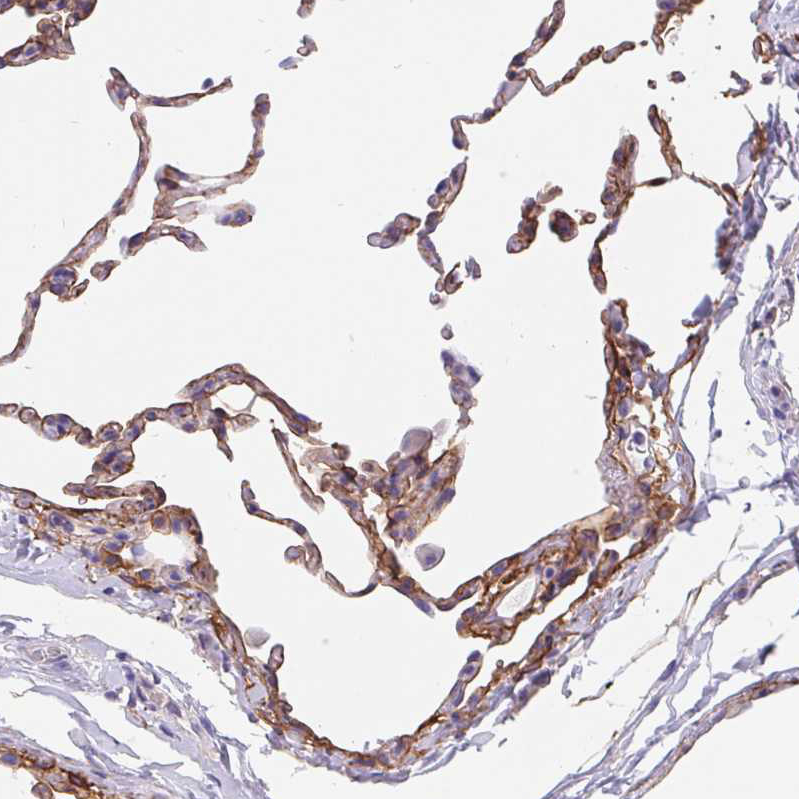

Immunohistochemical staining of human lung shows moderate cytoplasmic positivity in pneumocytes.